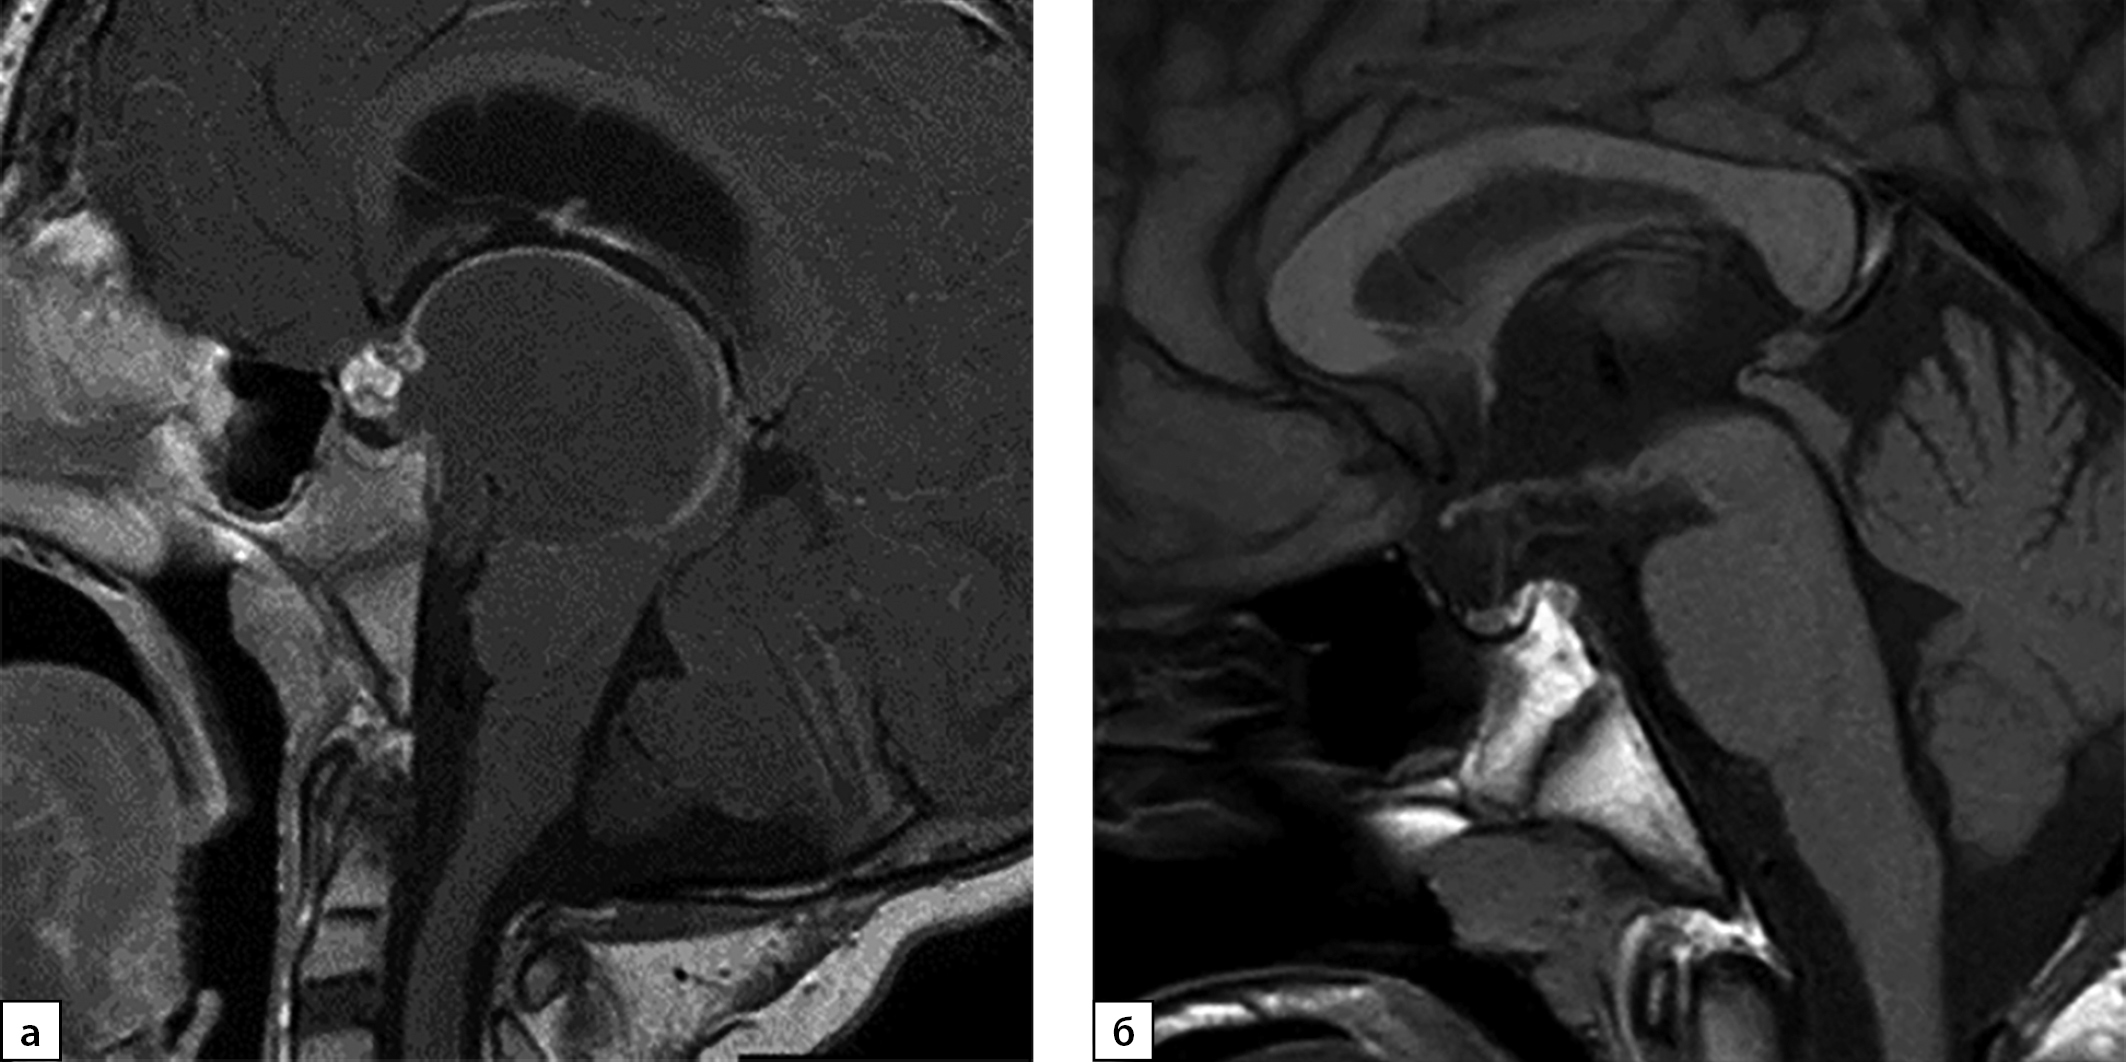

В возрасте 7 лет у мальчика появились головные боли с тошнотой и рвотой. Он был обследован, при МРТ выявлена краниофарингиома (КФ) (рис. 1а). Была проведена операция — биопсия опухоли и установка системы Оммайя с эвакуацией кистозного содержимого с последующей протонотерапией. После лечения развился вторичный гипотиреоз, по поводу которого назначена заместительная терапия препаратом левотироксина.

В дальнейшем пациент находился под наблюдением нейрохирурга (рецидива опухоли не было, рис. 1б) и эндокринолога по месту жительства. Исследование функции ГР не проводилось в связи с нормальными темпами роста (рис. 2). В 14 лет рост замедлился до 2 см в год, что послужило причиной обращения к эндокринологу в НМИЦ нейрохирургии им. акад. Н.Н. Бурденко.

Рисунок 1. МРТ пациента с КФ (а — до операции, б — на момент обращения).